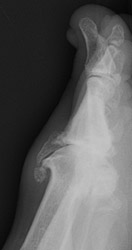

Osteoarthritis: Lateral View - Large dorsal osteophytes at 1st MTP jointOsteoarthritis: AP View - Large osteophytes and joint space narrowing at 1st MTP jointOSTEOARTHRITIS non-inflammatory deterioration of articular cartilage with articular surface and marginal bone formation.

Radiographic manifestations may include marginal osteophyte and subchondral bony cyst formation, eburnation, and interosseous joint space narrowing. First metatarsal phalangeal joint osteoarthritis is frequently associated with hallux valgus deformities. Calcaneal spurs, when manifested, are sharp and well defined.